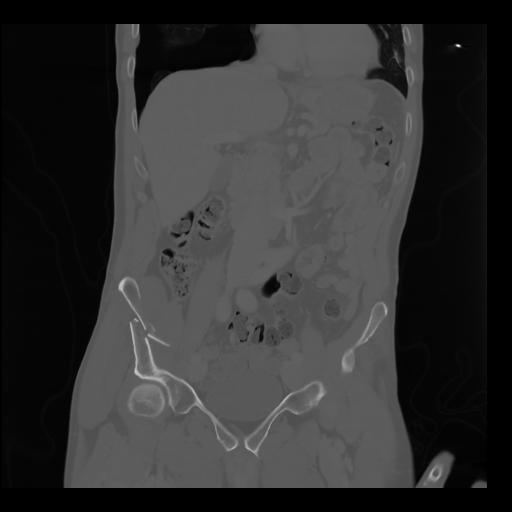

35 CUERPO,CE,Coronal,3.000,CUERPO,Coronal,